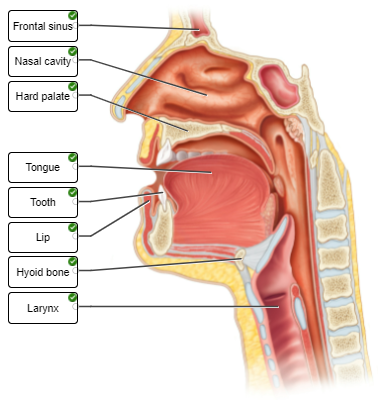

Label the features of the head and neck in the midsagittal section.